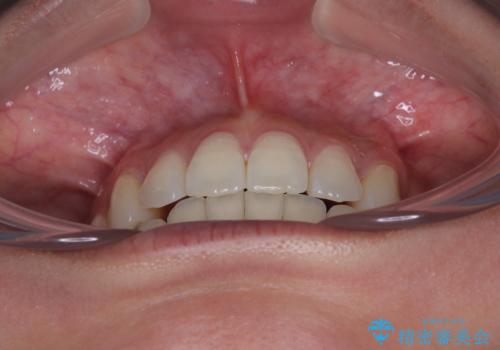

横顔は元々突出した印象ではなかったのですが、上顎前歯の角度が改善したことで、唇の閉じにくさが改善されました。